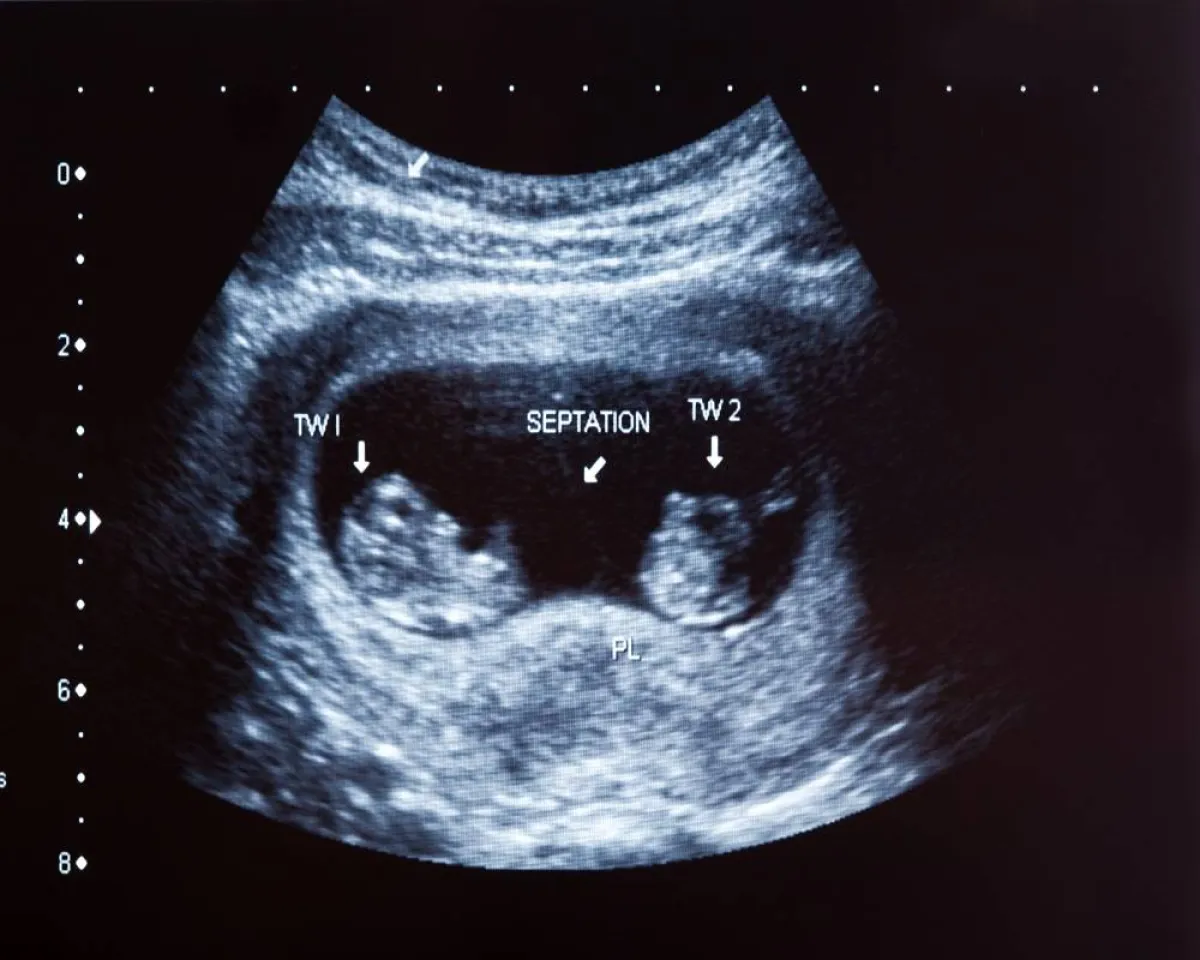

7-الموجات فوق الصوتية

الطريقة الوحيدة لتأكيد الحمل بتوأم هي الفحص بواسطة الموجات فوق الصوتية في وقت مبكر من ستة إلى سبعة أسابيع من الحمل.